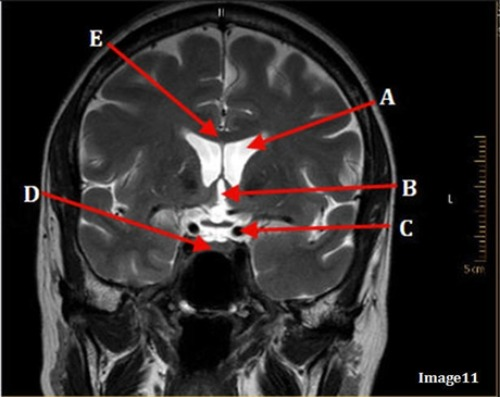

Image 11 is an example of a _______ weighted sequence acquired in the _______ scan plane.

D. T2; Coronal